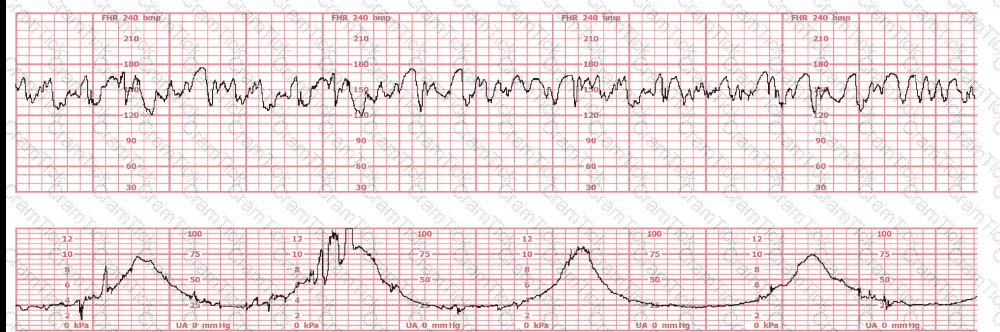

A 30-year-old woman (G2P0) is experiencing preterm labor at 26-weeks gestation. She is receiving magnesium sulfate for neuroprotection. Her external fetal monitoring tracing over the past 30 minutes is shown. The next step would be to: